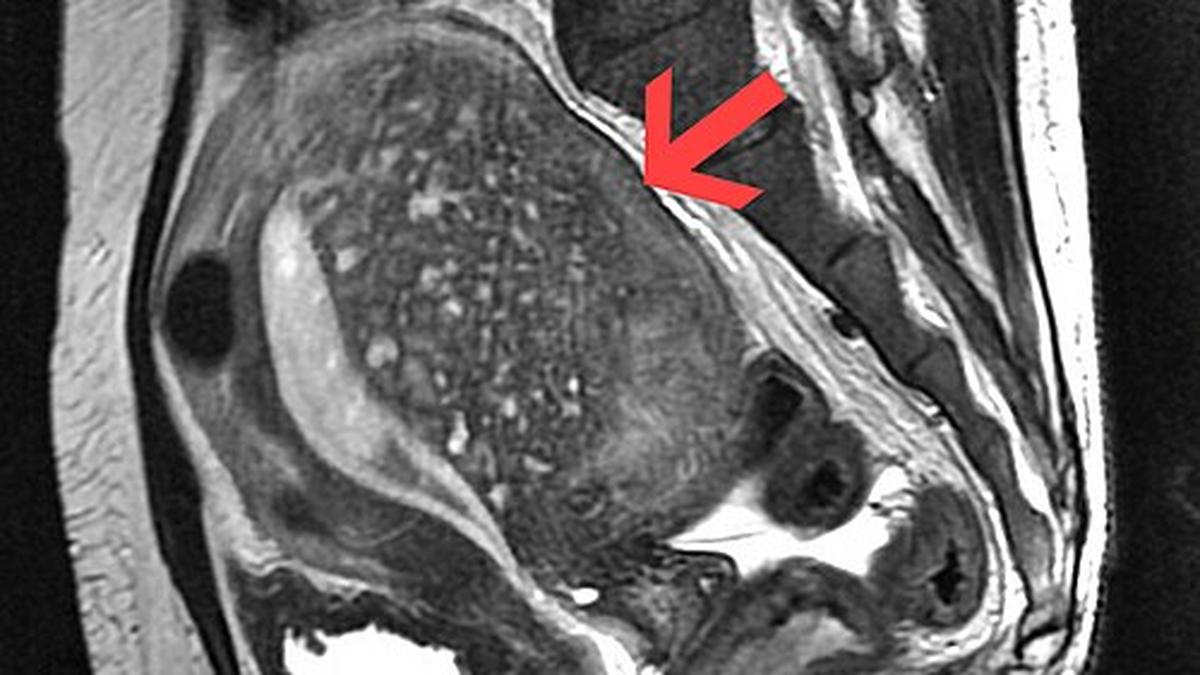

Despite being relatively common, adenomyosis remains under-recognised, with many women receiving a diagnosis only after years of symptoms